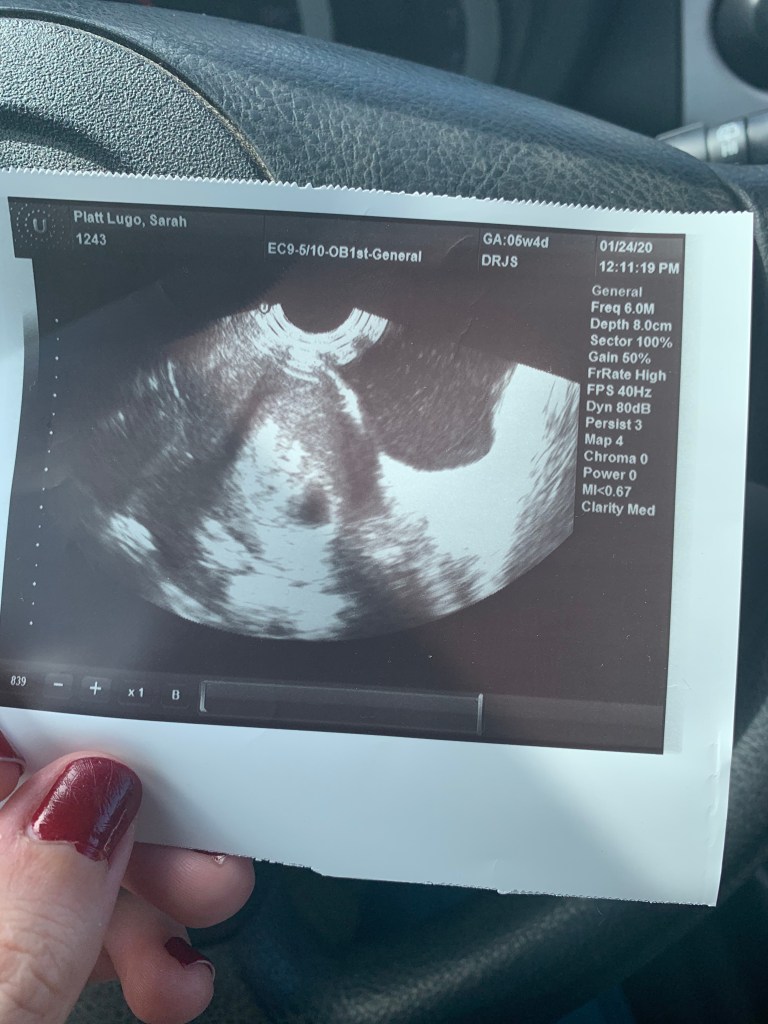

Cuando te vi por primera vez a través de una pantalla en la oficina del doctor, tenías cinco semanas de existencia, la forma de corazón y eras del tamaño de un grano de arroz. No eras humano todavía, sino la esperanza en formación de uno. Ese embrión que vi fotografiado en la ecografía ya se ha convertido en un futuro ser humano del tamaño de una cabeza de coliflor y en el que pienso a cada paso. Ya estás pronto a nacer. Lo hemos logrado y estará todo bien. A esa ilusión me aferro.